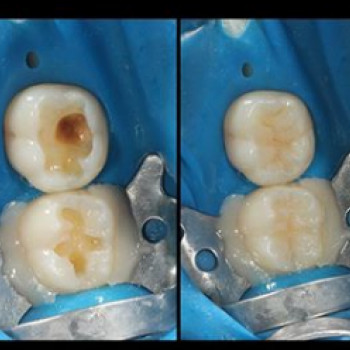

Лікування кореневих каналів — важливий етап для збереження зуба з ушкодженим нервом. Тут зібрані клініки та стоматологи, що проводять професійне ендодонтичне лікування.